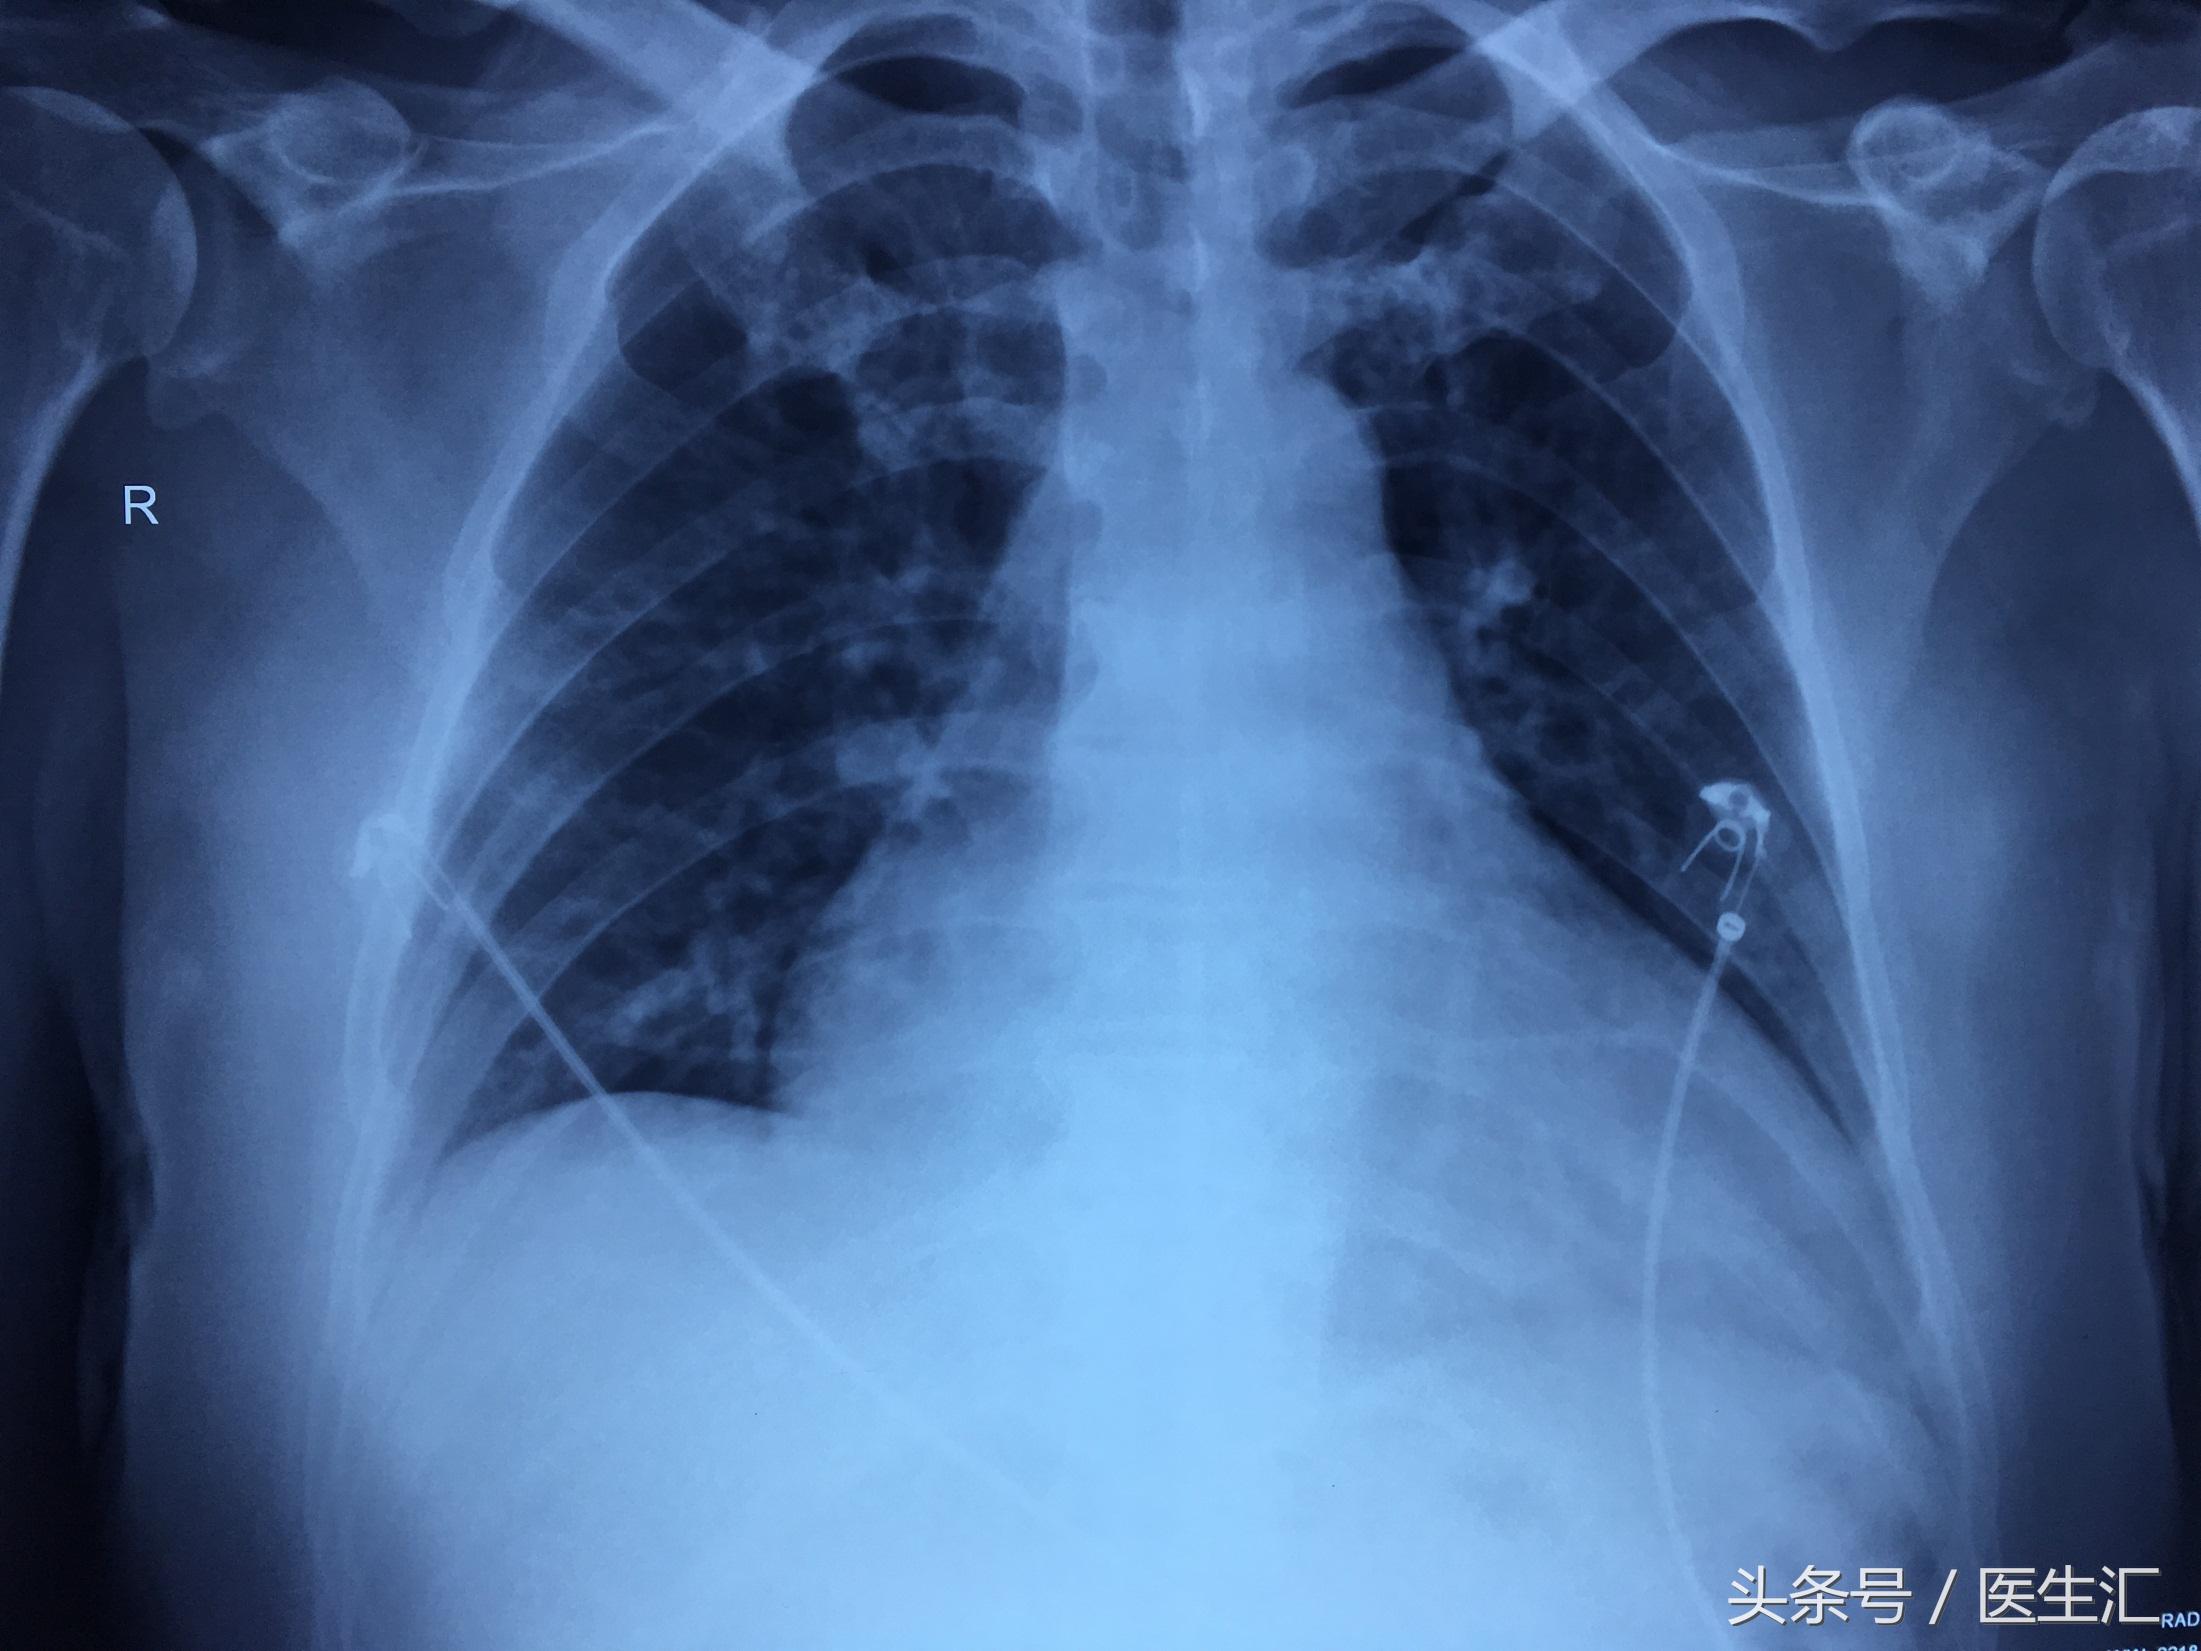

胸片示:

2017-02-24:双肺渗出,心功能不全可能。

2017-02-25:右肺渗出较前吸收,余大致同前。